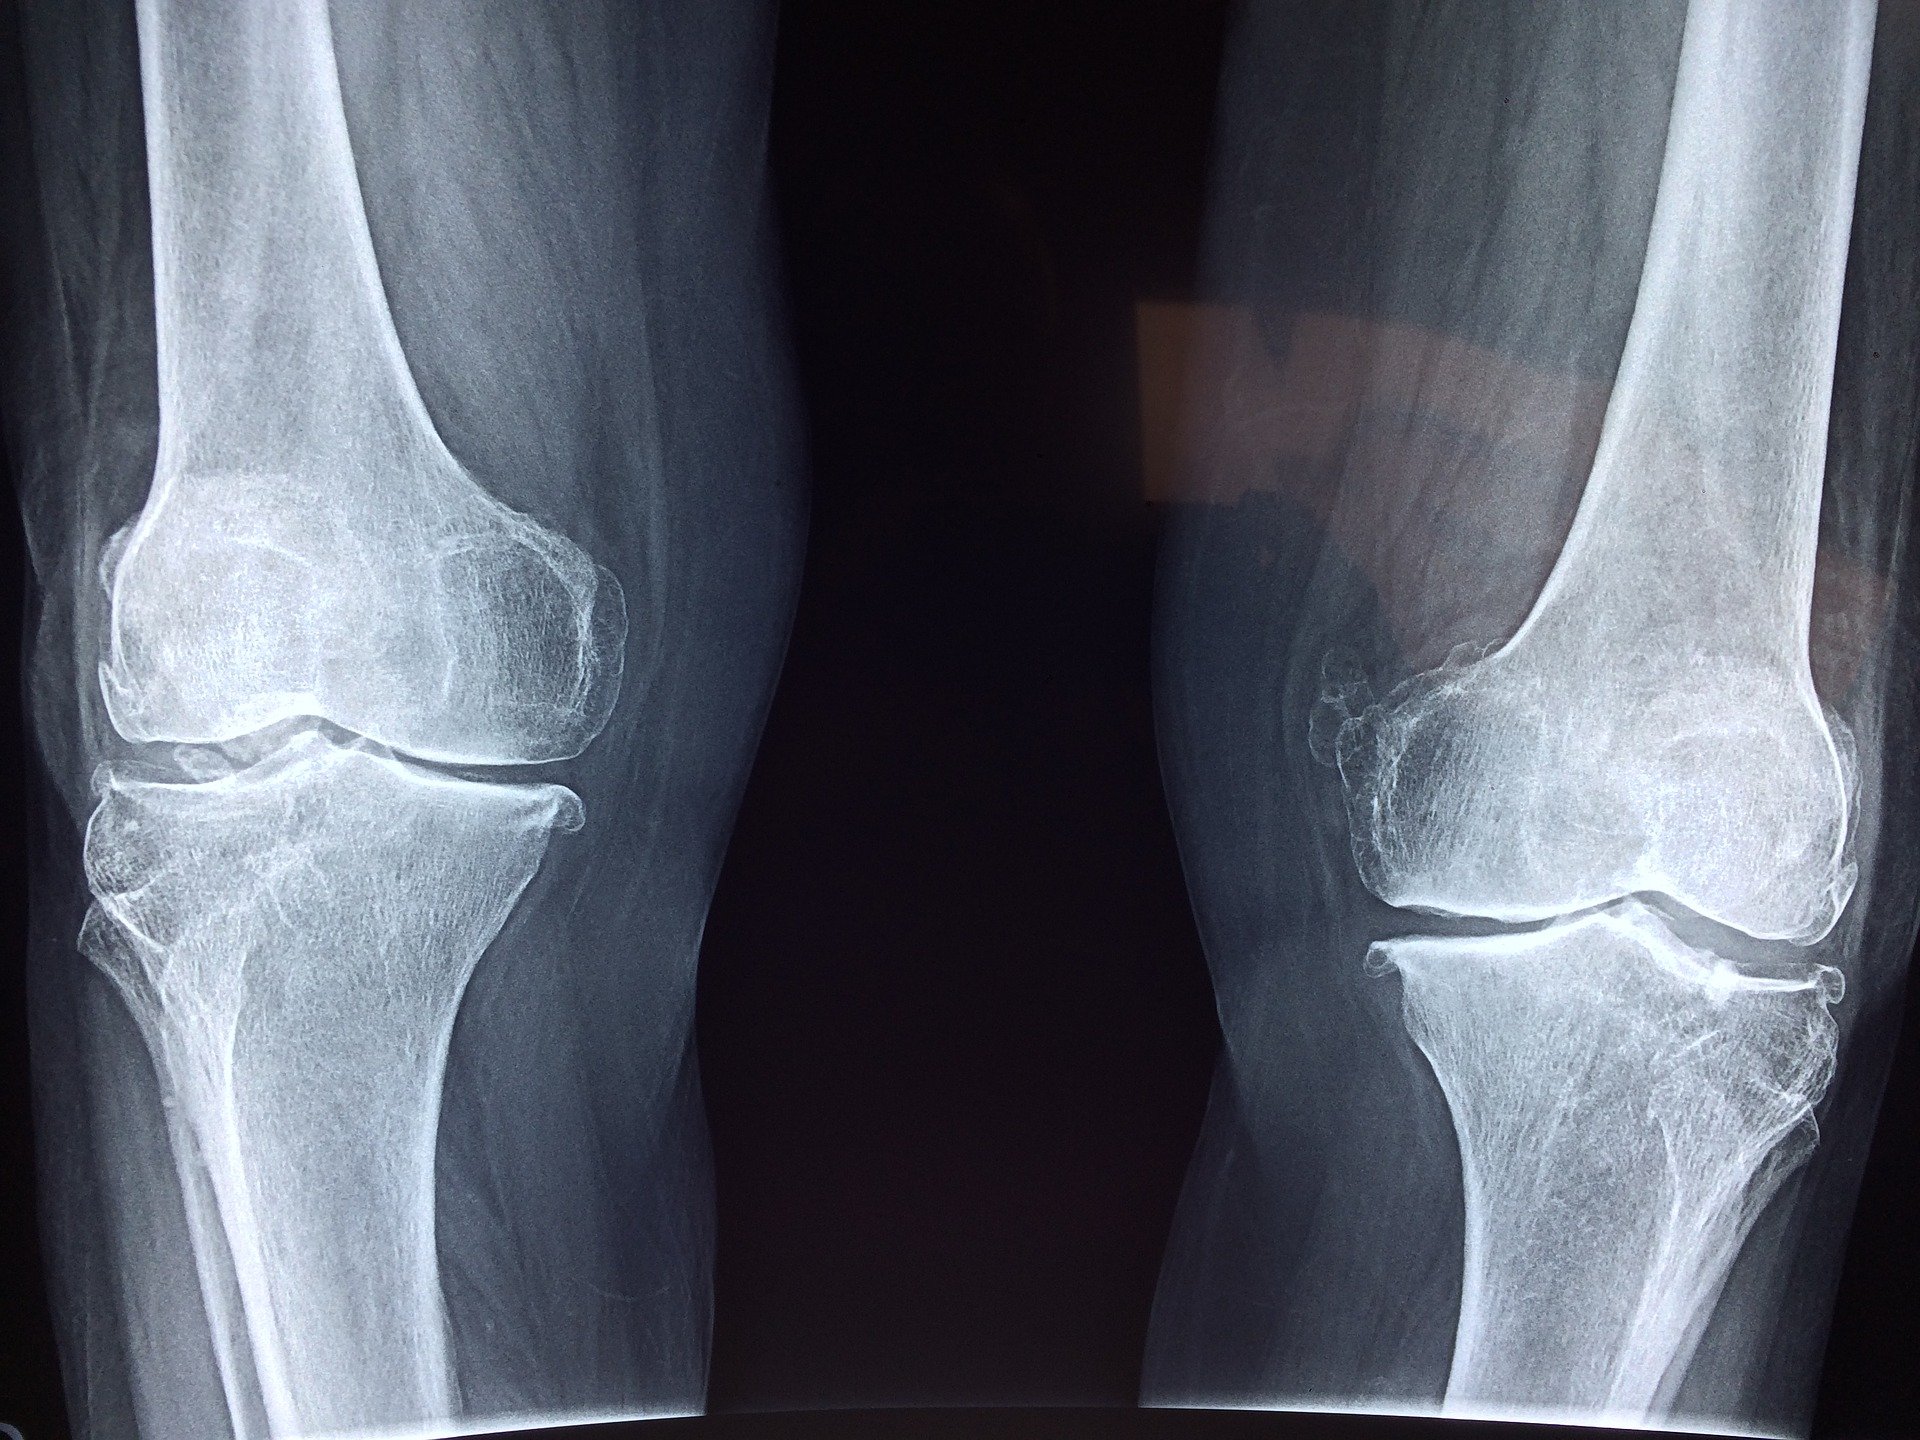

O to bardzo stara metoda stosowana niejednokrotnie przez sportowców, która pomaga w obrzękach oraz podczas uporczywych bóli kolan.

Oczywiście spuchnięte kolano może być początkiem różnych problemów na tle zdrowotnym i jeśli problem systematycznie nawraca bądź ulega zwiększeniu należy skonsultować swój problem z odpowiednim lekarzem. Ale jeśli na początku ból jest umiarkowany i chcemy spróbować domowych metod, które pomagają przy obrzękach i redukują ból można ich spróbować.